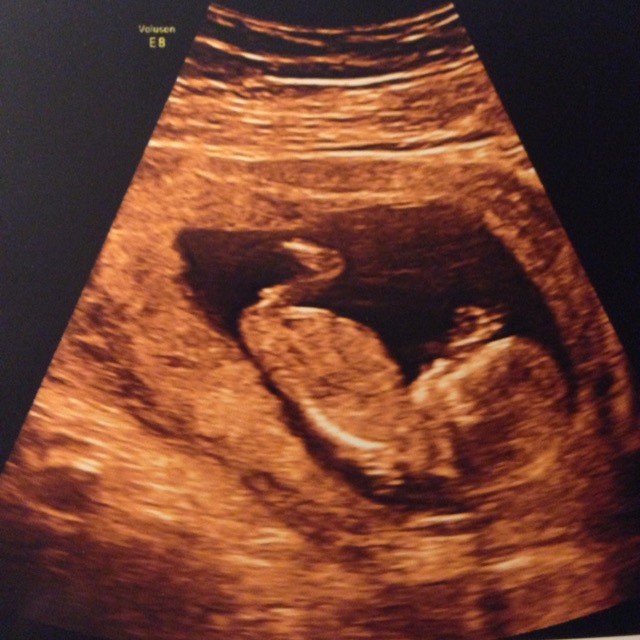

er ikke helt sikker på jeg forstår det der nub-teori, hvor og hvad skal man lige kigge på? Er ikke helt sikker på at der overhovedet er noget at se på billedet fra nf scanningen

Altså jeg vil sige dreng da jeg syntes det peger opad men hold mig lige opdateret det spændende

Det er så vidt vi ved fra kønsscanningen en lille pige